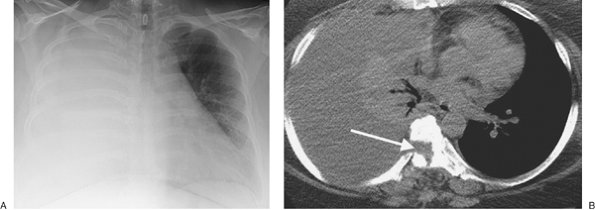

FIGURE 9-5. Cerebrospinal fluid leak into pleural space. A: PA chest radiograph of a 42-year-old man who recently underwent partial corpectomy of the thoracic spine at several levels shows complete opacification of the right hemithorax and shift of the mediastinum to the left. B: Non–contrast-enhanced CT shows a large right pleural effusion, collapse of the right lung, mediastinal shift to the left, findings of corpectomy, and continuity of fluid from the spine into the pleural space (arrow).